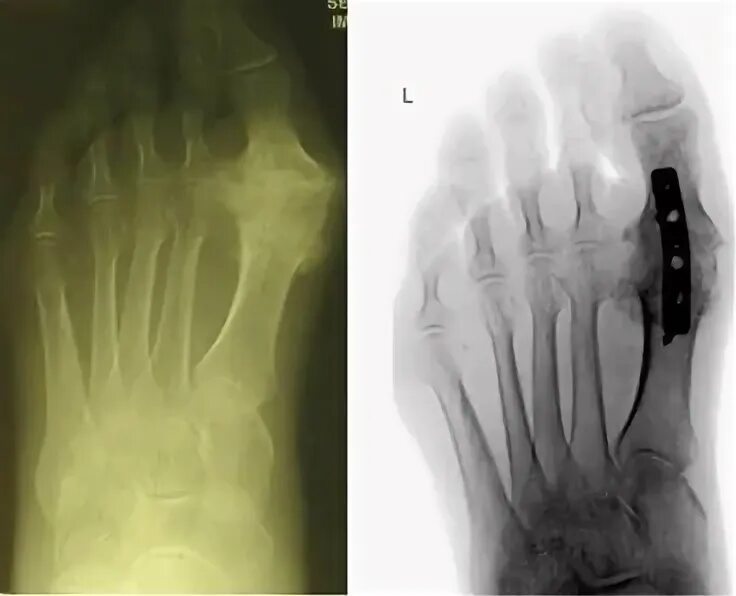

Артроз 1 степени плюснефалангового сустава стопы